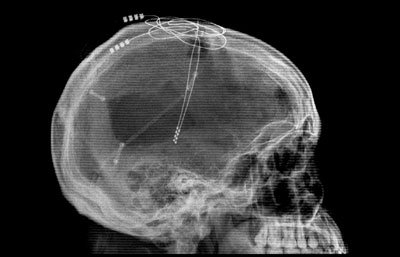

- A small pilot study of spinal cord stimulation for Parkinson’s found number of freezing-of-gait episodes reduced significantly from 16 (presurgery) to 0 (at 6 months post op) while subjects were on levodopa & off stimulation (Click here to read the research abstract, and click here to read a SoPD post on this topic).

An x-ray of the spine with a stimulator implanted (towards the top of the image, and cords leading off to the bottom left). Source:Wikipedia